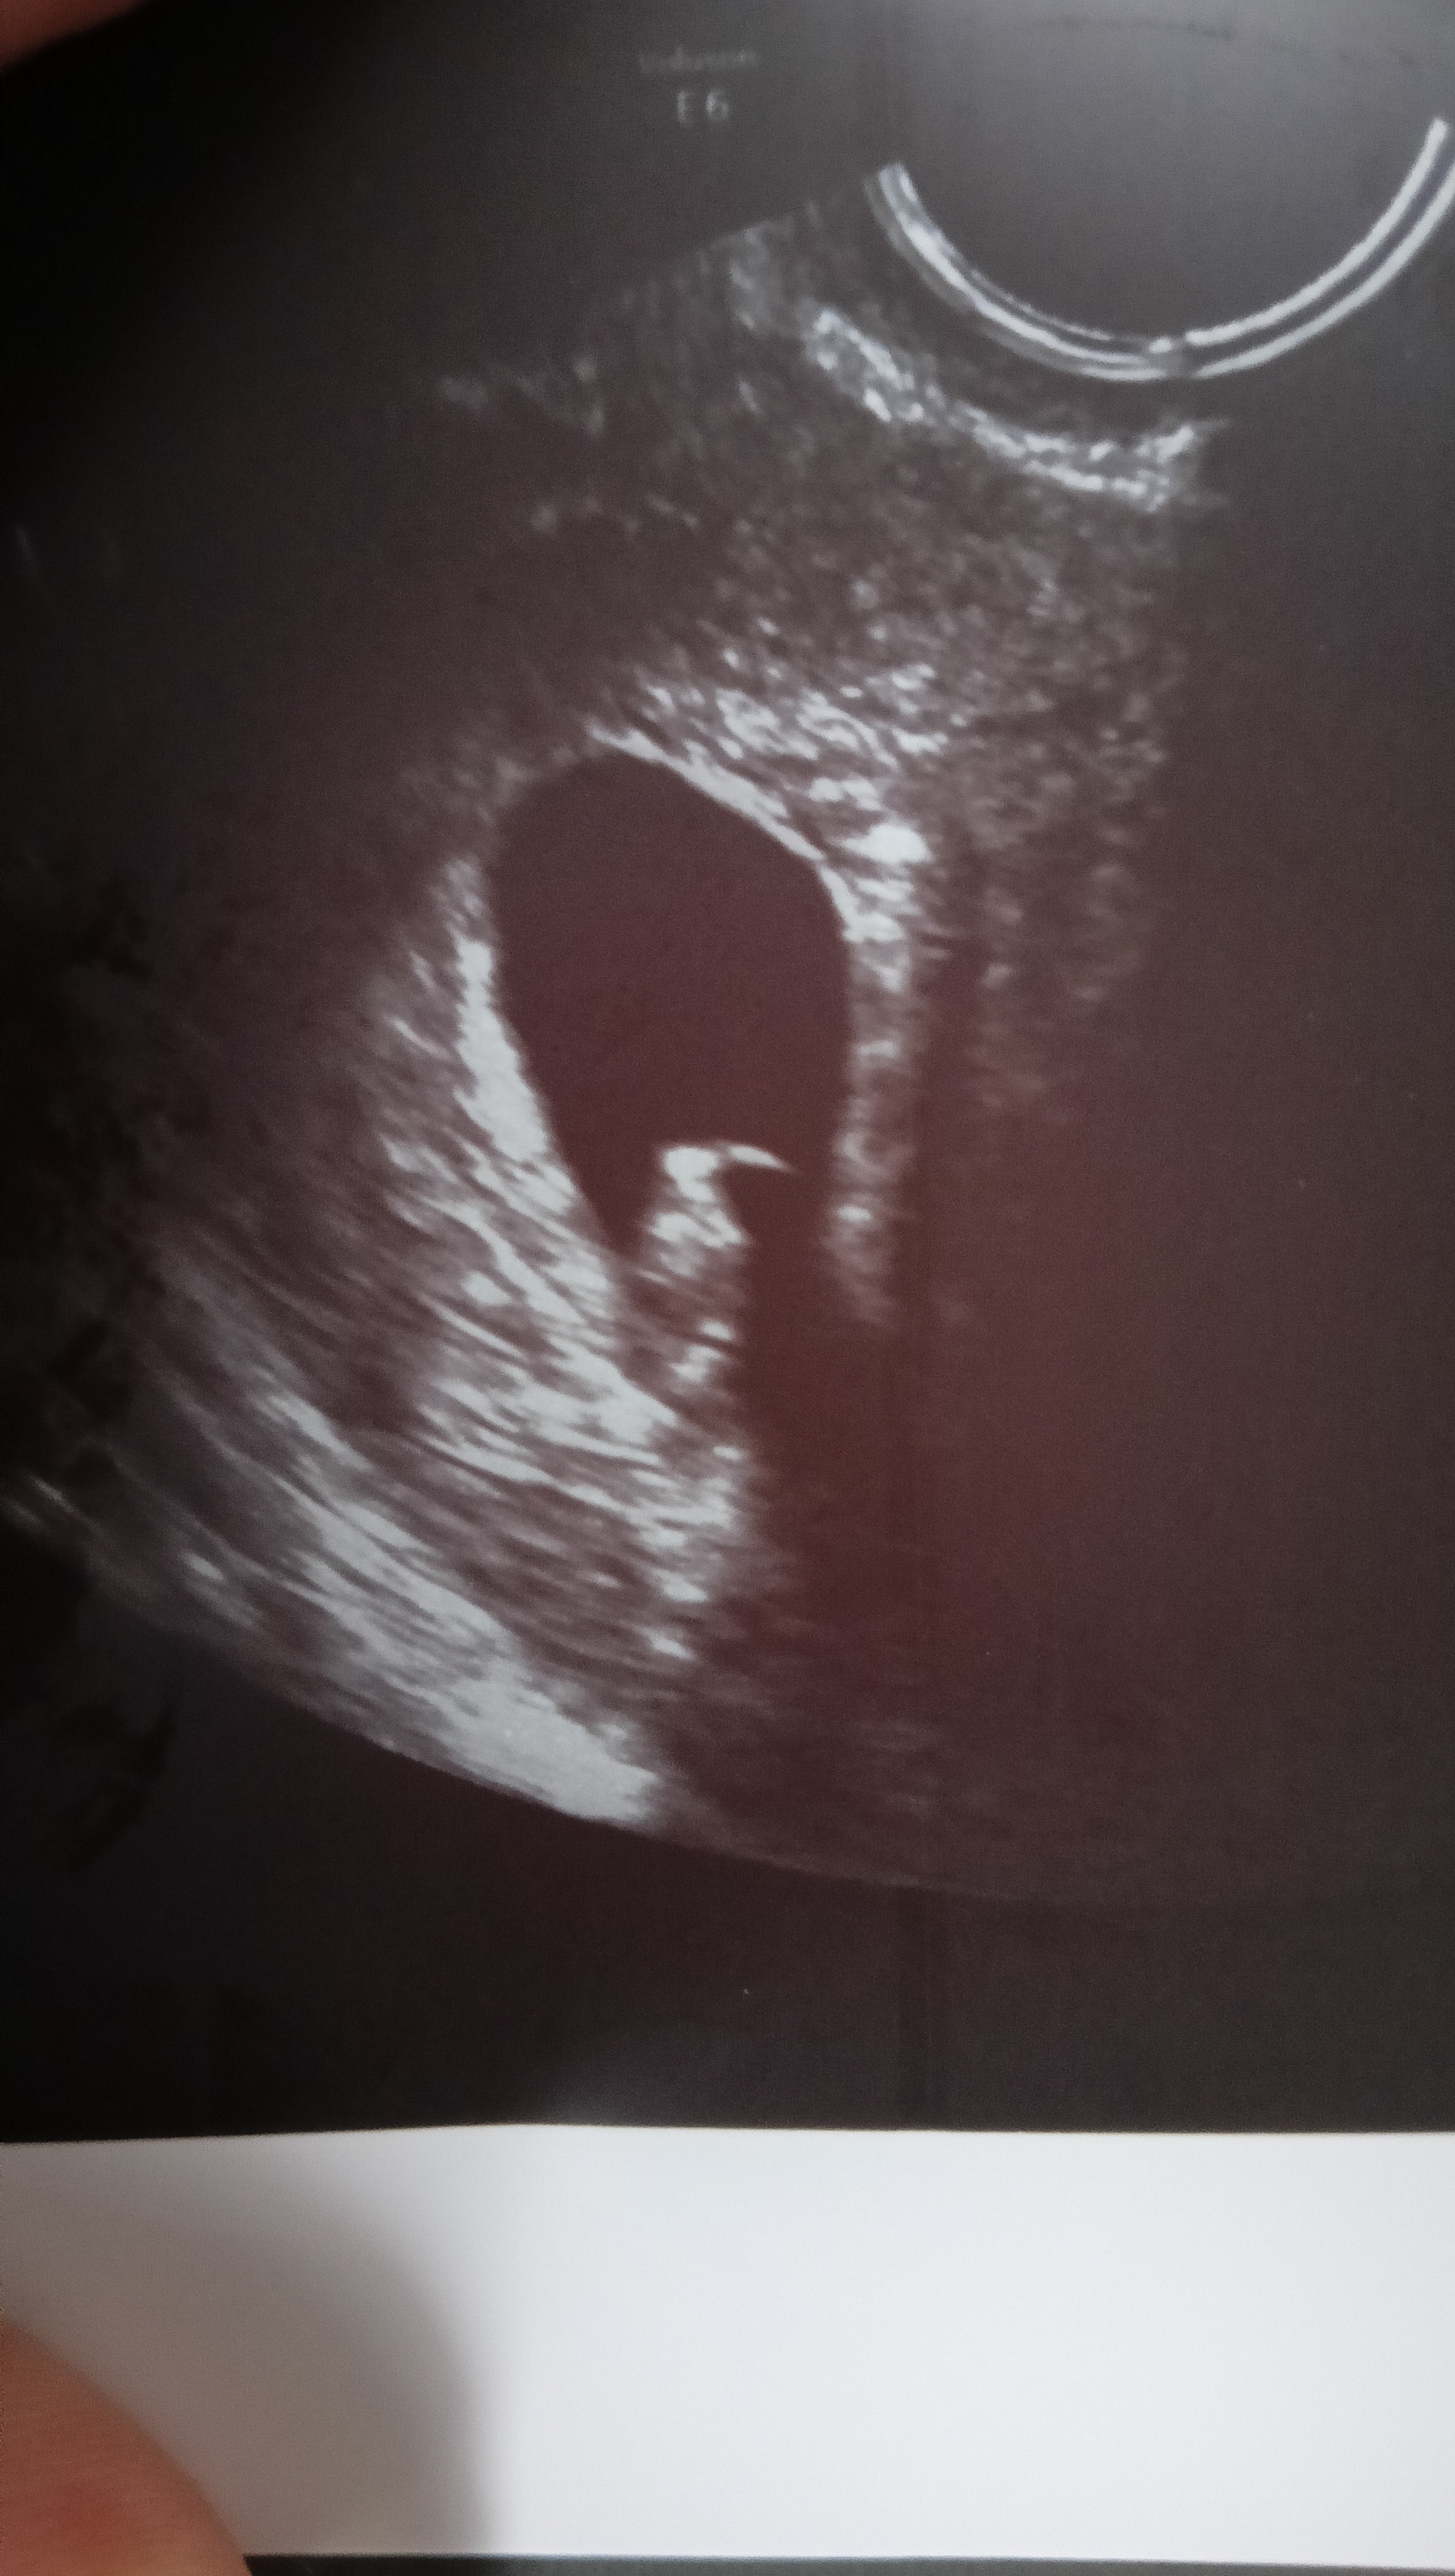

Ja po wizycie 😍serduszko bije mamy 1cm fasolki🥹 7+2🍀 🤞

Doktor anioł bardzo mily i wyrozumiały dokładnie zbadal w szyjce niema juz krwi niewiadomo skad to bylo. dostałam zalecenie zeby niedzwigac i odpoczywac . Mam brac wieksza dawke duphastonu a w razie czego jechac odrazu na ip.